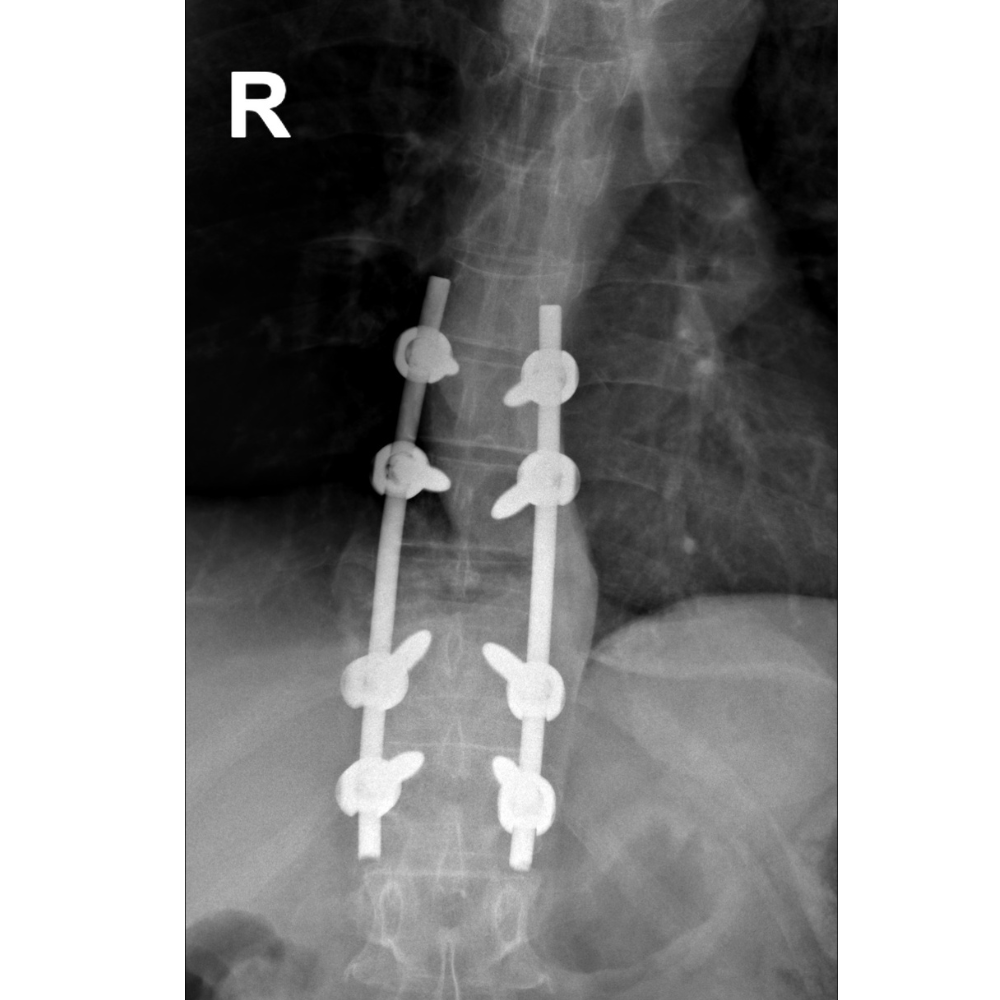

3. Spinal Stabilization: Use of rods, screws, or bone grafts to restore stability after tumor removal.

1. Pre-Surgical Evaluation: Includes imaging studies (MRI, CT, or X-rays), biopsy (if needed), and a thorough assessment of overall health.